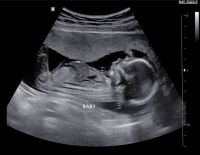

Siêu âm thai 6 tuần và tất cả những gì thai phụ cần biết

Siêu âm thai 6 tuần có thể là lần đầu tiên đi kiểm tra thai với nhiều thai phụ. Vì vậy, đây cũng là mốc đánh dấu quan trọng trong thai kỳ. Với những chia sẻ sau đây, các mẹ bầu sẽ có thêm những...